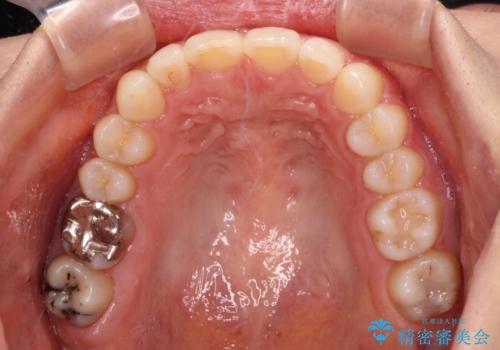

上下ともにデコボコの程度は著しいものではなく、インビザラインで十分に対応可能な歯列不正でした。

後戻りによりスペースができてしまうことを避ける目的で、IPR(歯と歯の間を削る)を極力用いない矯正治療を行うこととしました。